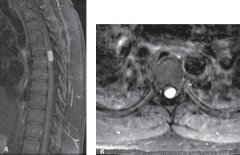

术中超声辅助治疗硬脊膜内脊髓

硬脊膜内肿瘤是一种重要的疾病,需包括在鉴别诊断患者的背...